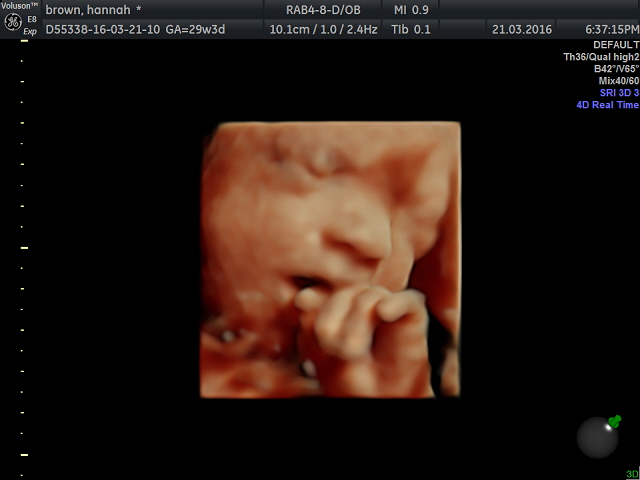

As they are so unique, the Heartbeat Bears caught my eye. You can have your own baby's heartbeat recorded, and then put inside a bear to keep forever. You could even give the bear to your baby when they arrive. After only ten minutes in the waiting room, we were called inside to the scanning room. The sonographer was lovely. She introduced herself and asked me for my due date before instructing me to lay down on the bed. The bed was covered with a soft purple blanket, making it comfier than an average hospital bed and made me feel much more relaxed. She applied the ultrasound gel to my stomach and began. First of all, we saw his little face in black and white while she checked his positioning. He was head down and wriggling like you wouldn't believe. She let us watch him play around for a short while which was incredible. He had his eyes wide open and was yawning away whilst opening and shutting his mouth the entire time! He was kicking himself in the head and rubbing his eyes with his tiny little hands. The cutest thing was when he was trying to find his mouth with his thumb and smiling away as he did so. It really was such a surreal experience watching him and catching a glimpse on his life inside the womb.

The photos are incredible. You can tell that the sonographer really knew what she was looking for and she really was amazing at her job. You could see her patiently waiting for the scanner to pick up the best photo and straight away she would click away and get the most amazing quality photos. Me and Will were sat in amazement at the details and clearness of every single photo taken. Even the DVD is so clear and you can see each part of his little body in such strong detail. His little feet, hands and all his beautiful facial features. We also got to listen to his heartbeat, and the lady took measurements of all his body. I asked if she could tell the weight of him (as the last scan he measured bigger) she told me you couldn't predict the weight but from measurements he was measuring bigger than average which does scare me a little!